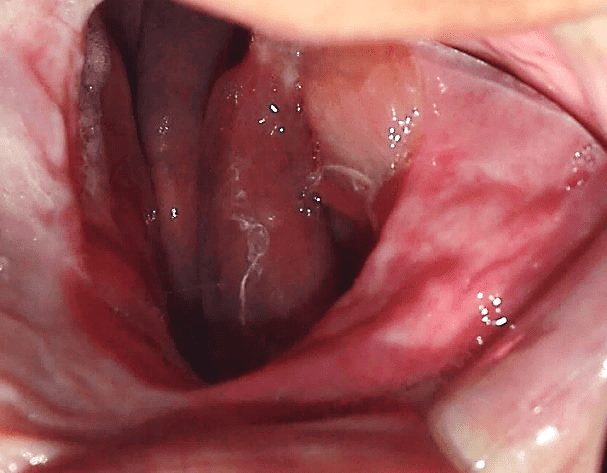

Thus, a new planning for rehabilitation was executed, having as a starting point the facial molding. The clinical sequence used was: skin cleansing by removing makeup and oiliness, protection of hair with bandage, application of solid vaseline in the facial hairs, tamponade of the nostols with cotton wool and a canudo for mouth breathing (figure 25). Then, the alginate (Jeltrate Dustless®, Dentsply, Argentina) was started using two parts, with the proportion of water/powder being 4:4. After being manipulated, it was deposited in small parts in the region to be molded with the aid of a spatula (figure 26), then the retention with cotton on the alginate was performed and the common plaster type II (Asfer®, Brazil) was added, in order to confer stiffness (figure 27), preventing deformation during its removal.

Figure 25: Preparation for the beginning of facial molding.

The mold was removed with slight movements, prompting the patient to move the mime muscles (figure 28). Immediately after molding, the mold was filled with type IV plaster (Durone®, Dentsply, Argentina) to obtain the facial model. With the aid of a vibrator, the plaster was deposited on the mold to prevent the formation of bubbles and when taking prey, the model was removed, so the finishes were executed (figure 29). Subsequent surgical removals, the treatment plan of choice was radiotherapy, being performed for two months, where it has already begun and is under medical follow-up.

Through histopathological examinations of the last surgeries performed on the patient, which indicated margin compromise, a more invasive surgery was planned by her physicians, which may compromise noble structures of facial support. Thus, facial molding was proposed, being as a guide for possible aesthetic-functional rehabilitation, after inavasive surgical procedure. The materials described in the literature for the preparation of facial molding are elastomers, hydrocolloides and plasters (AQUINO et al., 2012). The chosen technique is quite usual, low cost and easy execution, the material of choice for the case was irreversible hydrocolloside and plaster. Alsiyabi and Minsley (2006) mention that the conventional technique using irreversible hydrocolloide can result in inaccuracy and distortion of molding. Then, the authors propose the use of silicone, which will reduce clinical clothing and the fact that the material presents dimensional stability, deformation resistance and high tear resistance. On the other hand, the main disadvantage is the high cost of the material. Thus, facial molding performed with irreversible hydrocolloide proved to be effective, without distortions and low cost.